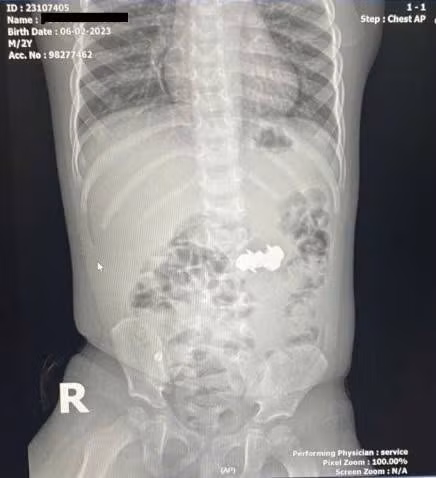

Trong thời gian dùng thuốc tại nhà, các triệu chứng không cải thiện, trẻ được tái khám và chụp X-quang phát hiện dị vật trong ổ bụng. Sau đó, trẻ được chuyển đến Bệnh viện Nhi Trung ương để tiếp tục theo dõi và điều trị.

Tại Bệnh viện Nhi Trung ương, sau khi thực hiện các xét nghiệm và chẩn đoán hình ảnh cận lâm sàng và theo dõi diễn biến, các bác sĩ nhận thấy dị vật trong đường tiêu hóa không di chuyển theo thời gian.

Thông thường, dị vật trong đường tiêu hóa sẽ được nhu động ruột đẩy dần ra ngoài. Tuy nhiên, trong trường hợp này, dị vật không di chuyển. Từ thông tin gia đình cung cấp về loại đồ chơi có các viên nam châm nhỏ có thể hút vào nhau, các bác sĩ chẩn đoán trẻ đã nuốt phải nhiều viên nam châm trong nhiều thời điểm.

vien-bi.jpg

Hình ảnh dị vật qua chụp X-quang và viên nam châm sau khi được các bác sĩ phẫu thuật lấy ra.